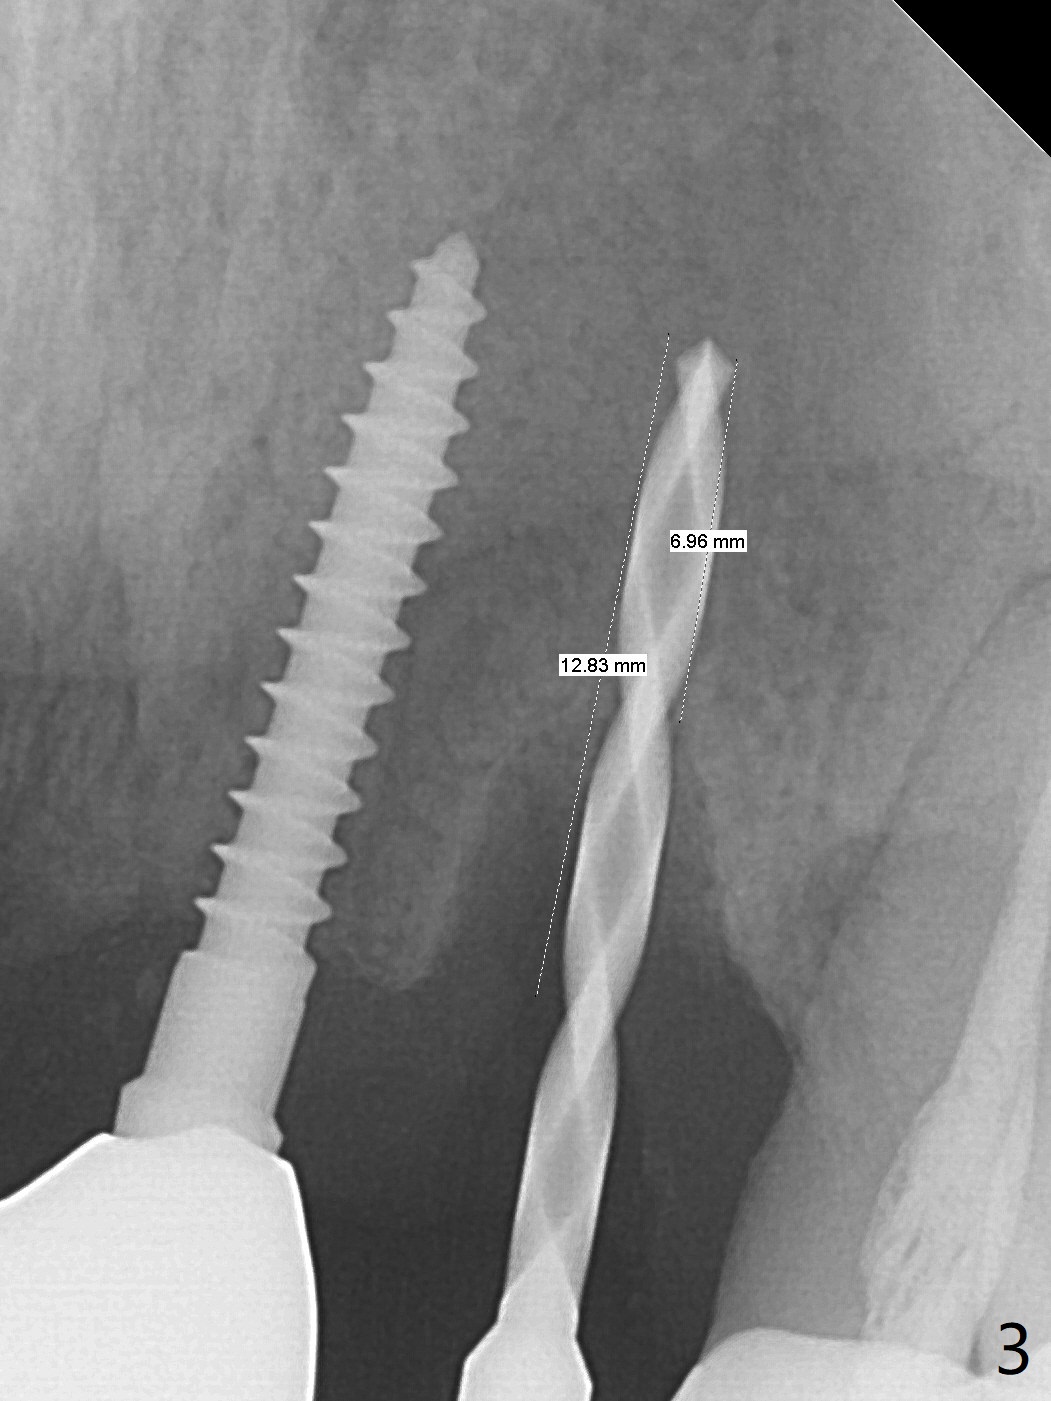

The tooth #10 has severe gingival recession (Fig.1) with loss of the buccal plate (Fig.2 *). After the initial osteotomy depth (Fig.3) increases by 2 mm, a 2.5x14(2) mm 1-piece implant is placed with insertion torque >60 Ncm (Fig.4). Palpation indicates the native bone apparently wider than CT shows. There is no sign of buccal or palatal plate perforation by palpation during osteotomy or implant placement. Vera Graft is placed repeatedly around the coronal threads (Fig.5-7 *). An immediate provisional is fabricated to close the socket (Fig.8). The buccal plate appears to collapse 1 month postop (cortical plate graft apparently more appropriate in this case); the margin of the provisional is trimmed so that the gingiva may grow incisally (Fig.9). The provisional dislodges several times postop due to short abutment. By nearly 4 months postop, the coronal bony defect seems to have been repaired (Fig.10 *). The tooth #11 has tenderness with bone loss (Fig.10 ^), corroborated by CT (distal bone loss, Fig.11 *). Since the apical bone is narrow (Fig.12), a narrow long implant is expected (Fig.13). Use an implant (3.5x13 mm) consistent with those at #14 and 15.